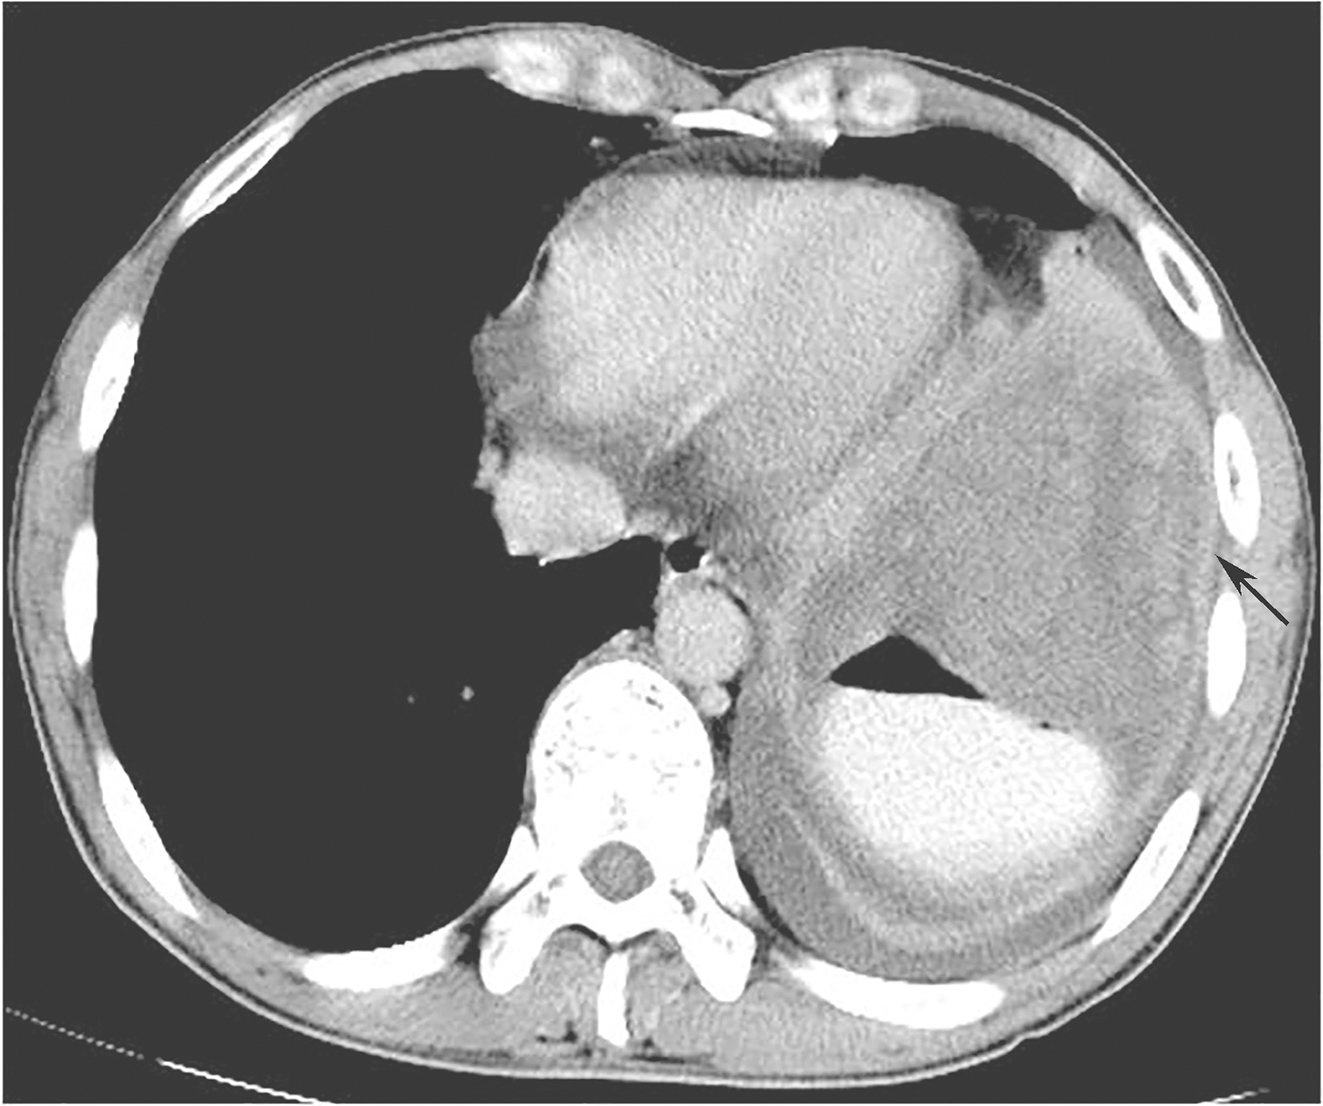

全腹部增强CT:左上腹软组织肿块,大小约16.4cm×12.3cm,考虑胃底大弯侧来源GIST伴左侧膈肌侵犯可能性大,需与淋巴瘤、神经鞘瘤、平滑肌瘤等其他胃黏膜下少见肿瘤鉴别(图1、图2)。

图1首诊全腹增强CT示胃底大弯侧来源GIST